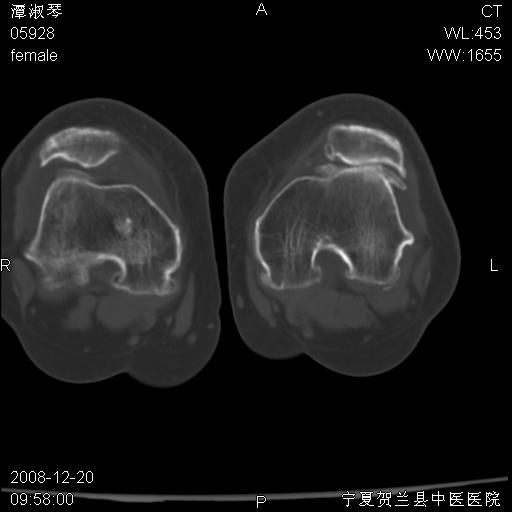

标题: CT17526:请各位看看是啥?

内生软骨瘤?骨梗死?

考虑内生软骨瘤可能性大

考虑-----骨梗死+退变

支持骨梗死,退行性骨关节病,膝关节积液.

考虑骨梗死可能性大

骨梗死可能性大

左股骨下段骨梗死。双膝退变。

左胫骨下端松质骨及髓腔内可见点片状高密度灶,骨皮质无明显膨胀及变薄。病变范围较长。支持骨梗死,退行性骨关节病,膝关节积液